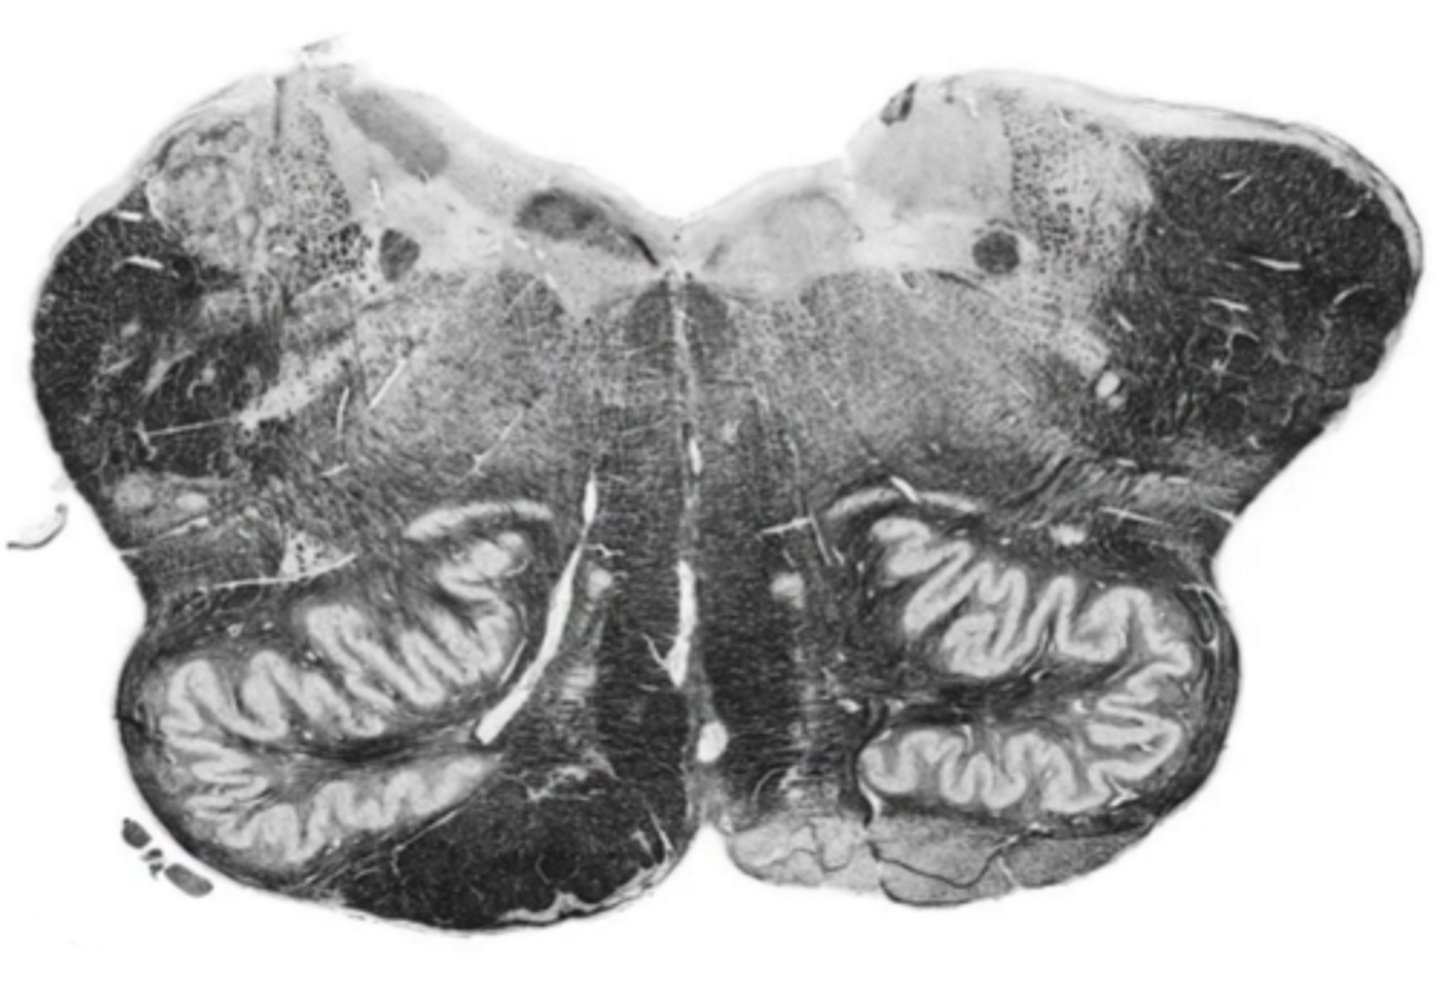

open medulla

ID the brainstem level

fourth ventricle

ID the space

ID the area

central gray

ID the structure

middle cerebellar peduncles

reticular formation

medial lemniscus

corticospinal fibers

pontine nucleus

ID the nucleus

vestibular nucleus

abducens nucleus

facial nucleus

facial nerve

ID the nerve

inferior cerebellar peduncles

olive

principle olivary nucleus

pre-olivary sulcus

anterior median sulcus

foramen of Luschka

cochlear nucleus

glossopharyngeal nerve